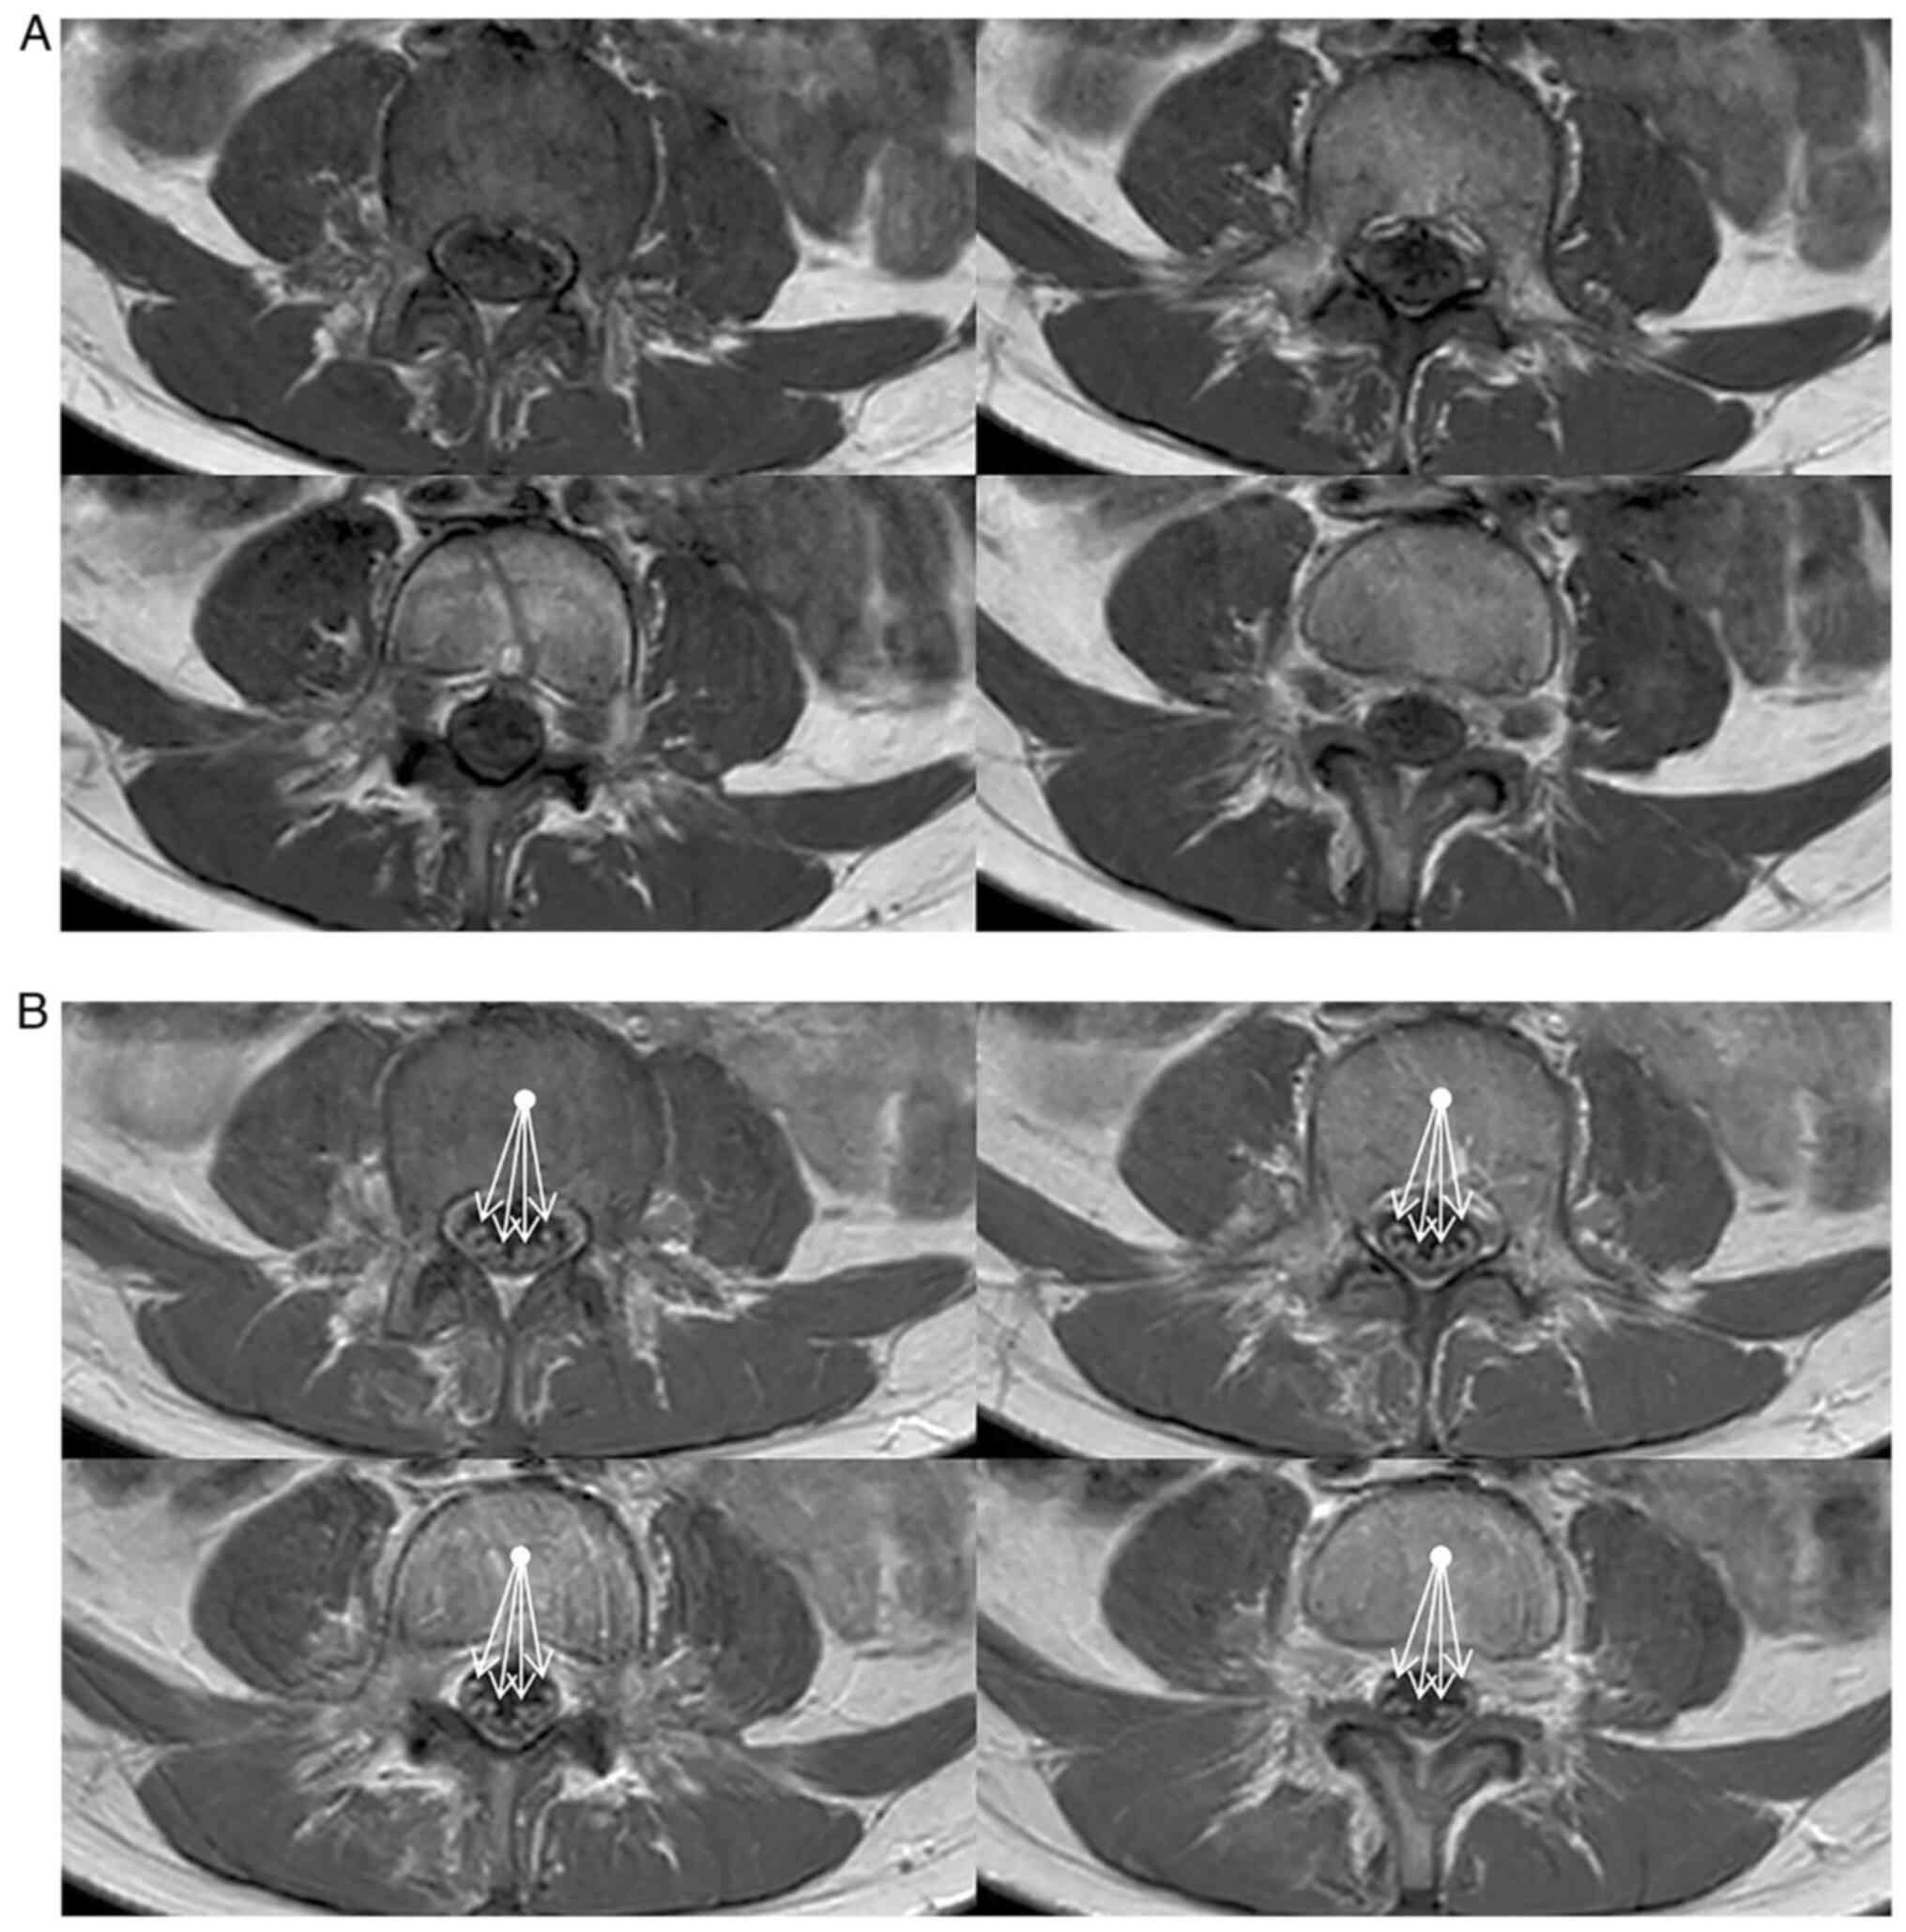

Cranial and spinal MRI (Philips Ingenia 1,5T; Spin-echo, Turbo Spin-Echo, Inversion Recovery, Gradient Echo, Echo Planar with T1, T2, DP weighted sequences, pre and post-contrast) showed marked enhancement of cauda equina roots after contrast injection, both in the sagittal (Fig. 1) and axial (Fig. 2) views, according to the clinical hypothesis of Guillain-Barré polyradiculonevritis.

Figure 2

Axial T1w turbo spin echo (A) pre- and (B) post-contrast magnetic resonance imaging showing marked contrast enhancement of cauda equina roots, suggestive of Guillain-Barré syndrome, is indicated by the arrows in (B).

Spinal MRI of our girl showed marked enhancement of cauda equina roots (Figs. 1 and 2).